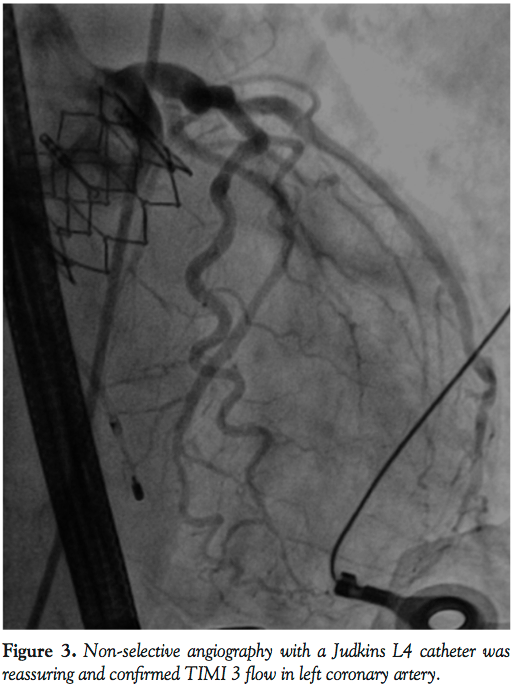

1A-1C). However, the patient remained hemodynamically stable with no electrocardiographic changes and a 26 mm Edwards SAPIEN XT valve (Edwards Lifesciences) was then positioned using fluoroscopic and TEE guidance and deployed, under burst pacing, in a good anatomical position. TEE confirmed a satisfactory position with minimal paravalvular regurgitation and improvement in ventricular function. Aortic root angiography suggested the presence of calcified mass close to, but not obstructing, the left coronary ostium (Figure 2). To examine the LMS more closely, a Judkins left 4 catheter was employed. The catheter did not engage the LMS, but non-selective angiography showed a patent LMS with TIMI 3 flow (Figure 3). As the patient remained hemodynamically stable with no electrocardiographic changes, sheaths were removed and the arteriotomy at the femoral artery was closed successfully with the 2 Proglide sutures. Following reversal of anesthesia, the patient was extubated uneventfully and transported to the nearby coronary care unit (CCU) for close observation.

She remained hemodynamically stable for 3.5 hours when she became abruptly hypotensive and breathless. Immediate trans-thoracic echocardiogram excluded pericardial effusion, but showed severe hypokinesia of the antero-lateral walls of the left ventricle. Abdomen was soft with no evidence of blood loss at femoral access sites. She then developed cardio-respiratory arrest and manual cardiopulmonary resuscitation (CPR) was commenced. LMS occlusion was now felt to be the most likely explanation for acute decompensation and emergency